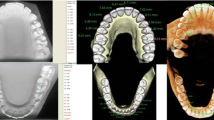

The first protocol involved manual image segmentation procedures on a 2D slice-by-slice basis through the use of Avizo's ‘lasso’ tool, which allows one to define an area freehand by generating a closed contour curve in 2D. The delineation of tooth structure from the surrounding alveolar and cortical bone was first determined on a slice-by-slice basis in the YZ (sagittal) plane (Figure 1) based upon visual inspection only. Refinements in the XY (axial) plane (Figure 2) were then manually completed for the observation of the tooth anatomy from a different perspective. An axial view enabled root structure and interproximal contact point refinements. Finally, additional refinements in the XZ (coronal) plane (Figure 3) were again manually completed. A coronal view enabled refinements to root structure that was in close proximity to the buccal and palatal cortical plates. The 3D resultant tooth was evaluated for approximately normal maxillary first molar dental anatomy to limit gross misidentification of dental structures (Figure 4). Once segmentation was completed, the software automatically computed the tooth's radiographic volume. No smoothing functions were applied to the 3D tooth structure to prevent smoothing of minor root defects/imperfections or possible resorption lacunae. Both the complete tooth volume (Figure 5A) and the dental root volume, defined as the anatomical root apical to the CEJ, (Figure 5B) were measured.

The second protocol involved the use of the ‘magic wand’ tool in Avizo 3D imaging software as a ‘region-growing’ tool. The ‘magic wand’ tool allows one to perform the so-called ‘region-growing’ in either 2D or 3D. Selecting an individual ‘seed voxel’ of a tooth root or crown selects the largest connected area (either 2D or 3D) that contains the voxel itself and all voxels with gray values contained within a user-specified range. The range can be chosen to represent absolute gray values or gray values relative to that of the seed voxel. For the purposes of our investigation, absolute gray values were chosen to limit variability in selection of the seed voxel gray value. Segmentation was performed using strictly an automated approach after minor operator input to the selection of the seed voxel in the enamel of the tooth without focused manual refinements in an attempt to test an efficient measurement procedure. The user input to select the seed voxel proved to be a necessity given the software. The rest of the procedure required no operator input for the actual segmentation procedure. A visually defined optimal threshold value was set for each tooth in the YZ (sagittal) plane (Figure 1). The threshold level was set to most clearly show the tooth anatomy with minimal interference from the surrounding bone and adjacent structures. The 3D resultant tooth was evaluated for approximately normal maxillary first molar dental anatomy to limit gross misidentification of dental structures. Once segmentation was completed, the software automatically computed the tooth's radiographic volume. As in protocol 1, no smoothing functions were applied and both the complete tooth volume and dental root volume were measured.

The third protocol also involved the use of the ‘magic wand’ tool in Avizo 3D imaging software as a ‘region-growing’ tool, similar to that utilized in the second protocol; however, in this case, segmentation was performed using a mixture of an automated approach with manual localized visual refinements to the tooth structure. For the purposes of our investigation, absolute gray values were chosen to limit variability in selection of the seed voxel gray value. The same absolute gray value range was selected as in the second protocol to limit variability between methods for each tooth. Segmentation was performed using a mixture of an automated approach with manual localized visual refinements to the tooth structure. A visually defined optimal threshold value was set for each tooth in the YZ (sagittal) plane (Figure 1). The threshold level was set to most clearly show the tooth anatomy with minimal interference from the surrounding bone and adjacent structures. Manual refinements were processed on a slice-by-slice basis to enhance accuracy by correcting for over- and under-contoured voxels in the tooth volume. Initial refinements occurred in the YZ (sagittal) plane. Secondary refinements were performed in the XY (axial) plane (Figure 2) to refine root structure and interproximal dental contact points. Tertiary refinements were performed in the XZ (coronal) plane (Figure 3) to verify tooth anatomy and focus on the delineation of dental root structure from the buccal and palatal cortical plates. The 3D resultant tooth was evaluated for approximately normal maxillary first molar dental anatomy to limit gross misidentification of dental structures. Once segmentation was completed, the software automatically computed the tooth's radiographic volume. As in protocols 1 and 2, no smoothing functions were applied and both the complete tooth volume and dental root volume were measured.